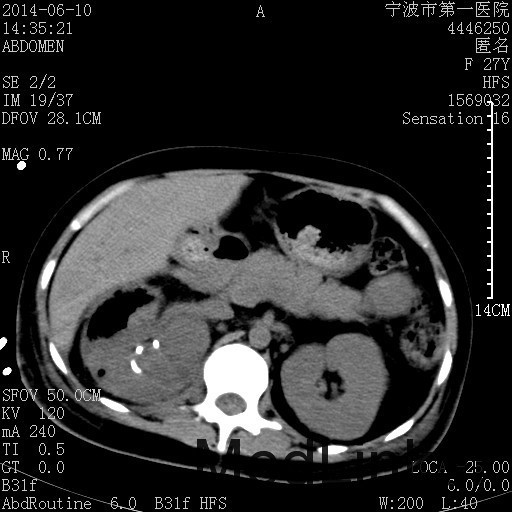

患者,女,27岁,因“右下腹疼痛伴呕吐2天”入院 患者无明显诱因出现右下腹疼痛伴呕吐、发热,体温最高39度,急诊CT示:右肾集气,考虑气性肾盂肾炎。

查体: 右肾区叩击痛,右下腹压痛,无反跳痛。 辅助检查: 空腹血糖9.7mmo/L,餐后血糖18mmol/L 血常规:白细胞 11.3*109/L, 中性百分比 77.4%, 血红蛋白 8g/L, 血小板 319*109/L 尿常规 WBC+++ 生化:白蛋白 37.5g/L,肝肾功能正常 泌尿系CT:右肾集气

诊断为“气性肾盂肾炎,感染性休克,糖尿病酮症酸中毒” 血、尿、脓液培养均示“克雷伯杆菌” 入院第2天行“右双J管置入术” 入院第3天、7天行“右肾穿刺造瘘术” 入院1月行“右肾切除术” 术后顺利康复出院。